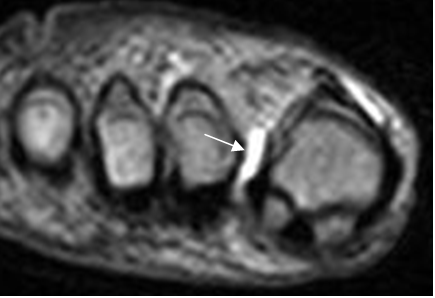

En la ecografía se encuentra como una lesión quística y en la RM, una lesión homogénea, hipointensa o con SI intermedia en T1, según su contenido de proteínas e hiperintensa en T2 y STIR. Muestra una cápsula fibrosa hipointensa, que puede realzar con el contraste. La lesión puede ser uni o multilocular y se puede identificar una cola que se dirige hacia tendón o articulación donde se origina. (1,5). (Fig 140).